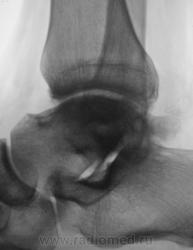

Пациент направлен на рентгенографию голеностопного сустава с диагнозом ДОА.

Травма была два года тому.

Похоже  на  остеохондропатию  блока  таранной  кости  +   ДОА.

А присутствует линейный (или лентовидный, я их путаю) остеопороз, а это признак острого процесса.

С учётом стрелочек, надо полагать, остеомиелит!..

Будем думать, что некроз блока таранной кости не такой уж и асептический, какая-то инхвекция там есть.

Посттравматический артроз с кистовидной перестройкойлатерального мыщелка Субхондральное уплотнение исужение суст. щелей естьИ неконгруэнтность большеберцового эпифиза к таранной маленько просматривается?